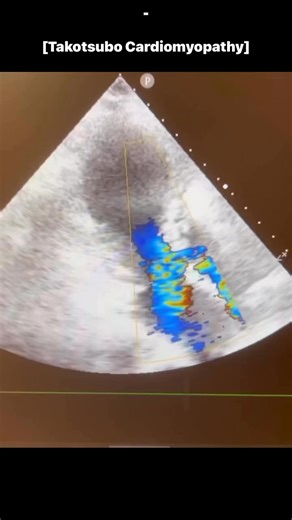

Cardiomyopathy - Takotsubo

Echocardiogram - Takotsubo

Echo - Takotsubo

Ultrasound - Takotsubo